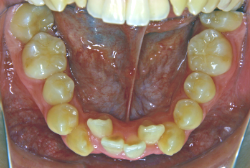

叢生(そうせい)

凸凹な歯並びのことを叢生といいます。矯正歯科に来院する患者様の主訴の中で、最も多いのが「配列の凸凹を真っ直ぐにしたい」というものです。歯の大きさと顎の大きさの調和がとれていないことが原因です。

凸凹を主体としたケースの場合、当院の平均治療期間は18ヶ月ですので、このケースは少し長めに経過しました。理由の一つは凸凹の程度がかなり重症だったと言うことですが、もう一つは、右下第2大臼歯が45度くらい前傾していたため、それを整直化させるために時間を要したと考えています。いずれにしても最終結果は大変よい状態と思います。

治療前は並びが乱れて見た目が悪いというのはもちろん問題ですが、歯科医学的に一番困るのは噛み合わせが悪いという点です。上下の犬歯(3番目の歯)は、上下的に離れた位置にあるため接触することができません。つまり歯としては存在していても、歯としては機能していないということです。